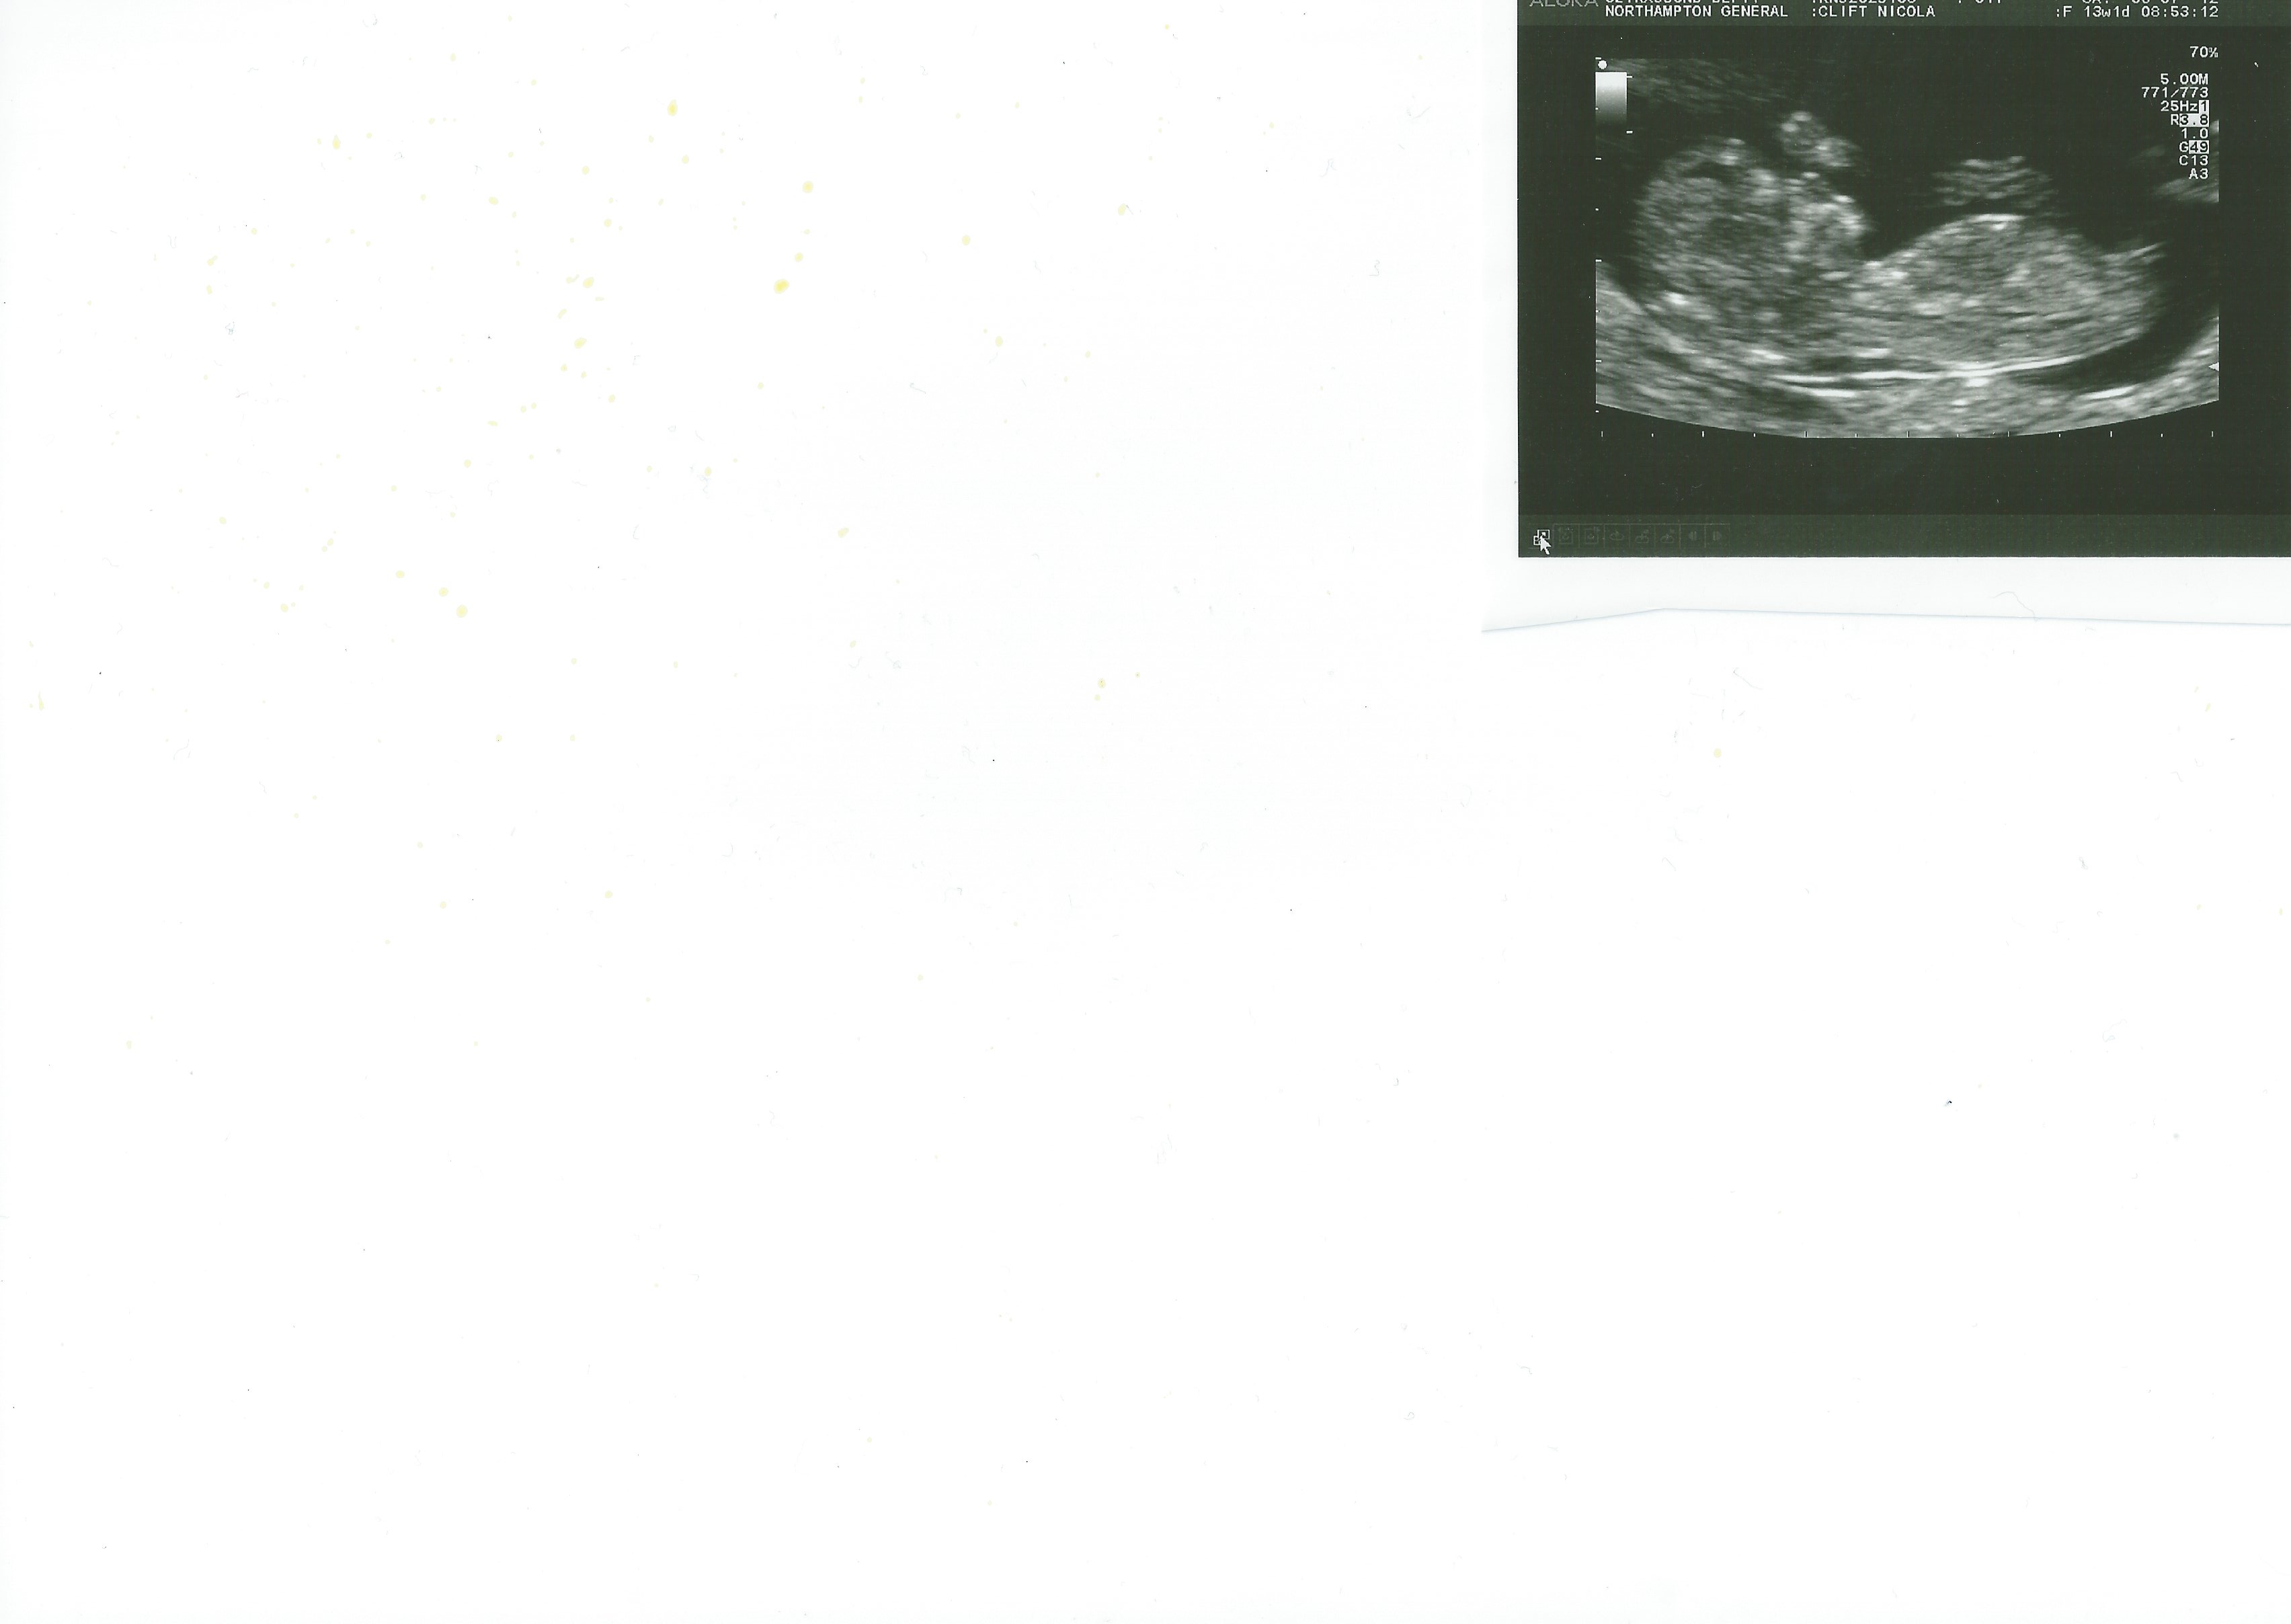

2nd pic

Attachment 3497

No expert but leaning blue

Girl

Looks almost identical to my dd's nub, so I say girl!!

I think girl

Boy by nub and skull 💙

leaning boy by skull and girl by nub....I know that doesn't help much, I am no expert but gooooood luck!!!!!